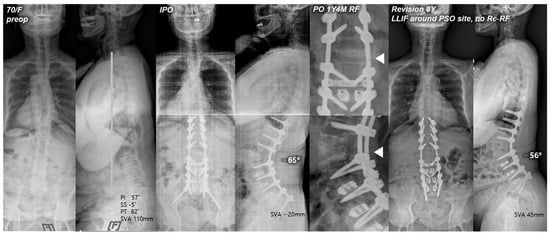

4.2. Bilateral Rod Replacement with LLIF around the PSO Site

None of the patients in the RR + LLIF group had experienced re-RF (Figure 2). This result can be attributed to the reduced residual sagittal motion of the construct, the increased stress distribution through anterior support, and the enhanced stability via interbody fusion immediately above and below the PSO site [22]. This finding was consistent with that of a cadaveric study by Deviren et al. [23] which showed increased stability through placement of interbody cages above and below the PSO site in multiaxial bending conditions. Luca et al. [8] also reported that the management of revision surgery after PSO may require an addition of anterior column support to maintain correction and reduce complications. In the same vein, Dickson et al. [24] recommended interbody fusion above and below the PSO site to help reduce the risk of further pseudarthrosis. Therefore, providing the anterior column support through interbody work around the PSO site by either a lateral or anterior approach may be a promising method for revision due to RF. However, further comparative studies are needed to assess the effectiveness of the LLIF technique with respect to the prevention of RF and postoperative complications.

Figure 2. Pre- and postoperative standing radiographs of a 70-year-old female patient. After T10-S1 posterior instrumentation with PSO on L2, and PLIF on L3-S1, optimal sagittal balance was achieved (SVA, −20 mm; TK, 12°; LL, −65°; PI, 57°; PT, 17°; SS, 40°). At 1 year and 4 months after primary deformity correction, RF (right rod) occurred at L2–3. At 8 years following revision surgery with bilateral rod replacement and LLIF around the PSO site, sagittal alignment was well maintained without re-RF. White triangles indicate the site of RF.